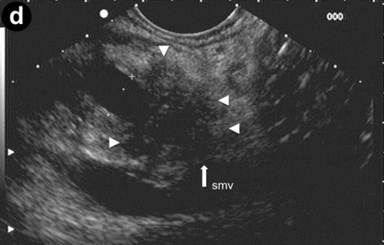

Patient#3: Focal form of autoimmune pancreatitis.

A 43-year-old man referred to us for abdominal pain and weight loss. IgG4 levels were elevated (298 mg/dL). Coronal scans with contrast enhanced CT (Image 3ab) showed the pancreatic head was enlarged with hypodense areas (2.7 cm, arrow) without vascular involvement of the mesenteric vessels. The pancreatic duct was dilated in both the body and the tail regions (arrowhead); the biliary tree was normal. The CT scan findings suggested pancreatic cancer. EUS and EUS-FNB were requested. Linear scanning (Image 3c) showed an enlarged pancreatic head with a focal hypoechoic mass (22 mm measured with calipers) with irregular margins (arrowheads). Upstream dilatation of the main pancreatic duct (8 mm, measured with calipers) in the body-tail regions was associated with the echopoor focal lesion (arrowheads); the lesion had close contact with the superior mesenteric vein (Image 3d). On EUS Doppler study (Image 3e), the echopoor lesion of the pancreatic head (arrowheads) appeared hypovascular; the superior mesenteric artery (arrow) and vein were patent.